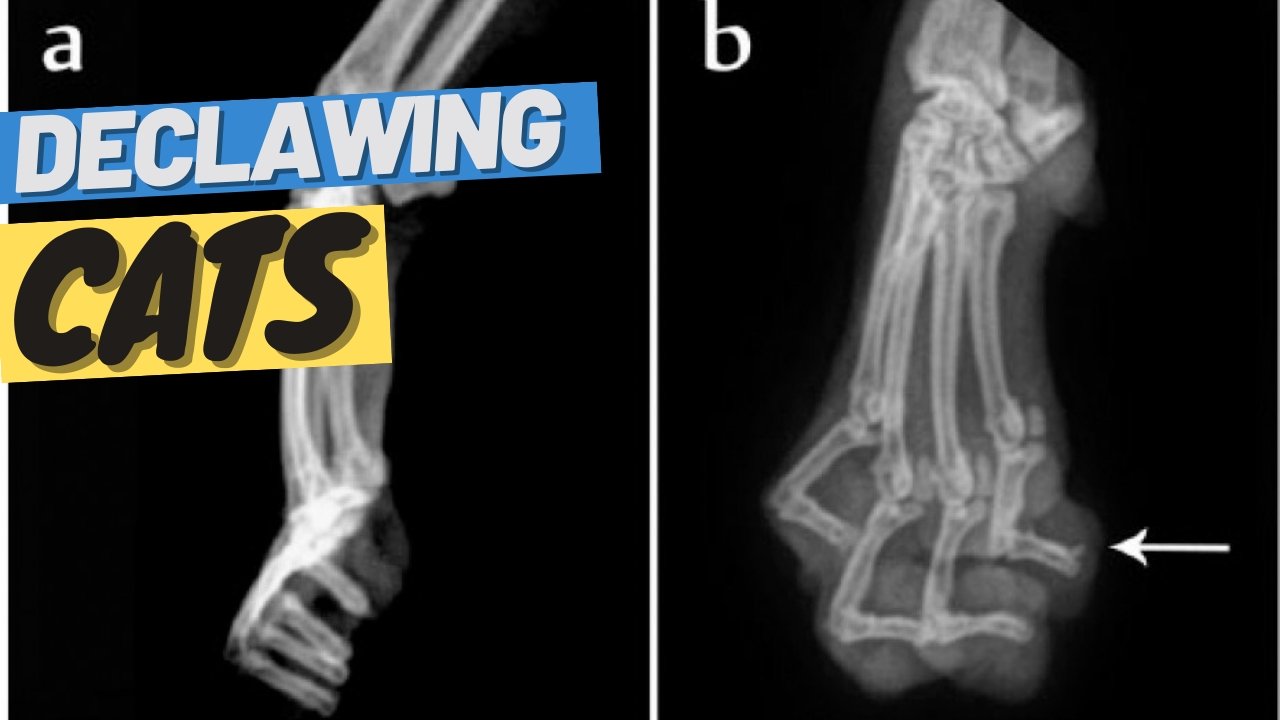

Feline declawing is an optional and ethically conflicting surgical procedure that is rarely medically necessary for cats. There are many misconceptions about declawing. While many think the procedure consists of removing the nail from the toes, the actual procedure is an amputation of the front part of the finger. The finger is broken into three separate bones P1, P2, and P3. The vet will articulate the last P3 bone from the two other bones.

This procedure consists of the amputation of the last bone of each toe. In more technical terms, the procedure of Onychectomy consists of the amputation of the distal phalanx.

The last procedure is called the Roscoe clipper technique or a guillotine technique. The vet will use a blade and cut through different ligaments. There is a high possibility of botch surgery, where the vet can break certain parts of the bone and leave that bone in tissue. It can cause a lot of pain and discomfort and potentially even a follow-up surgery.

Research done by the Journal of Feline Medicine and Surgery studied 137 declawed and 137 non-declawed cats.

They learned that declawing cats increases the risk of unwanted behaviors and may increase the risk of developing back pain. Evidence of inadequate surgical technique was common in the study population.

Among declawed cats, retained P3 fragments further increased the risk of developing back pain and adverse behaviors. The use of optimal surgical technique does not eliminate the risk of adverse behavior subsequent to onychectomy.

Also, removing the joint from the toes is very hurtful for the cats. Cats are tip-toe walkers meaning that they walk on their toes. The moment you perform this procedure, they go flat-footed immediately.